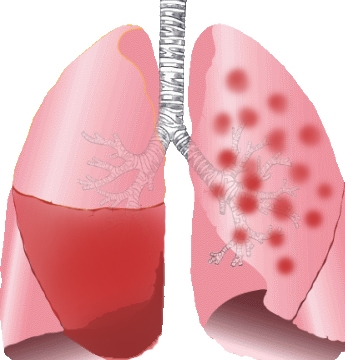

감기 발생 부위는 주로 코나 목 등 상기도가 원인 미생물이 감염되어 염증이 발생하는 것입니다. 이와 달리 폐렴 그 중 일반적인 폐렴의 경우는 폐 속의 감염으로 폐포라는 부위에 염증이 발생한 것을 말합니다.

폐포란 산소를 받아들이고 이산화탄소를 배출하는 호흡을 하고 있는 부분입니다. 따라서 이 폐포에 염증이 있으면 숨 쉬기가 힘들고 괴로우며 호흡이 빨라지고 가끔은 호흡곤란에 이르기도 합니다. 그리고 입원이 필요할만큼 중증이 되기도 있어서 미리 그 둘의 차이를 구분해야 합니다.

폐렴

발생 부위는 폐이며 중증의 경우는 입원이 필요합니다. 전형적인 증상은 대부분은 38도 이상의 고열과 기침, 노란색이나 녹색 가래, 숨가쁨, 가슴통증 등이 있습니다. 특히 가래 색깔은 폐렴 구균감염증은 적갈색 즉 녹슨 색깔의 가래를 볼 수 있습니다.

폐렴 원인은 폐렴구균, 인플루엔자균 등의 세균과 라이노바이러스, 인플루엔자바이러스, RS바이러스, 파라인플루엔자바이러스, 코로나 바이러스 등이 있습니다.